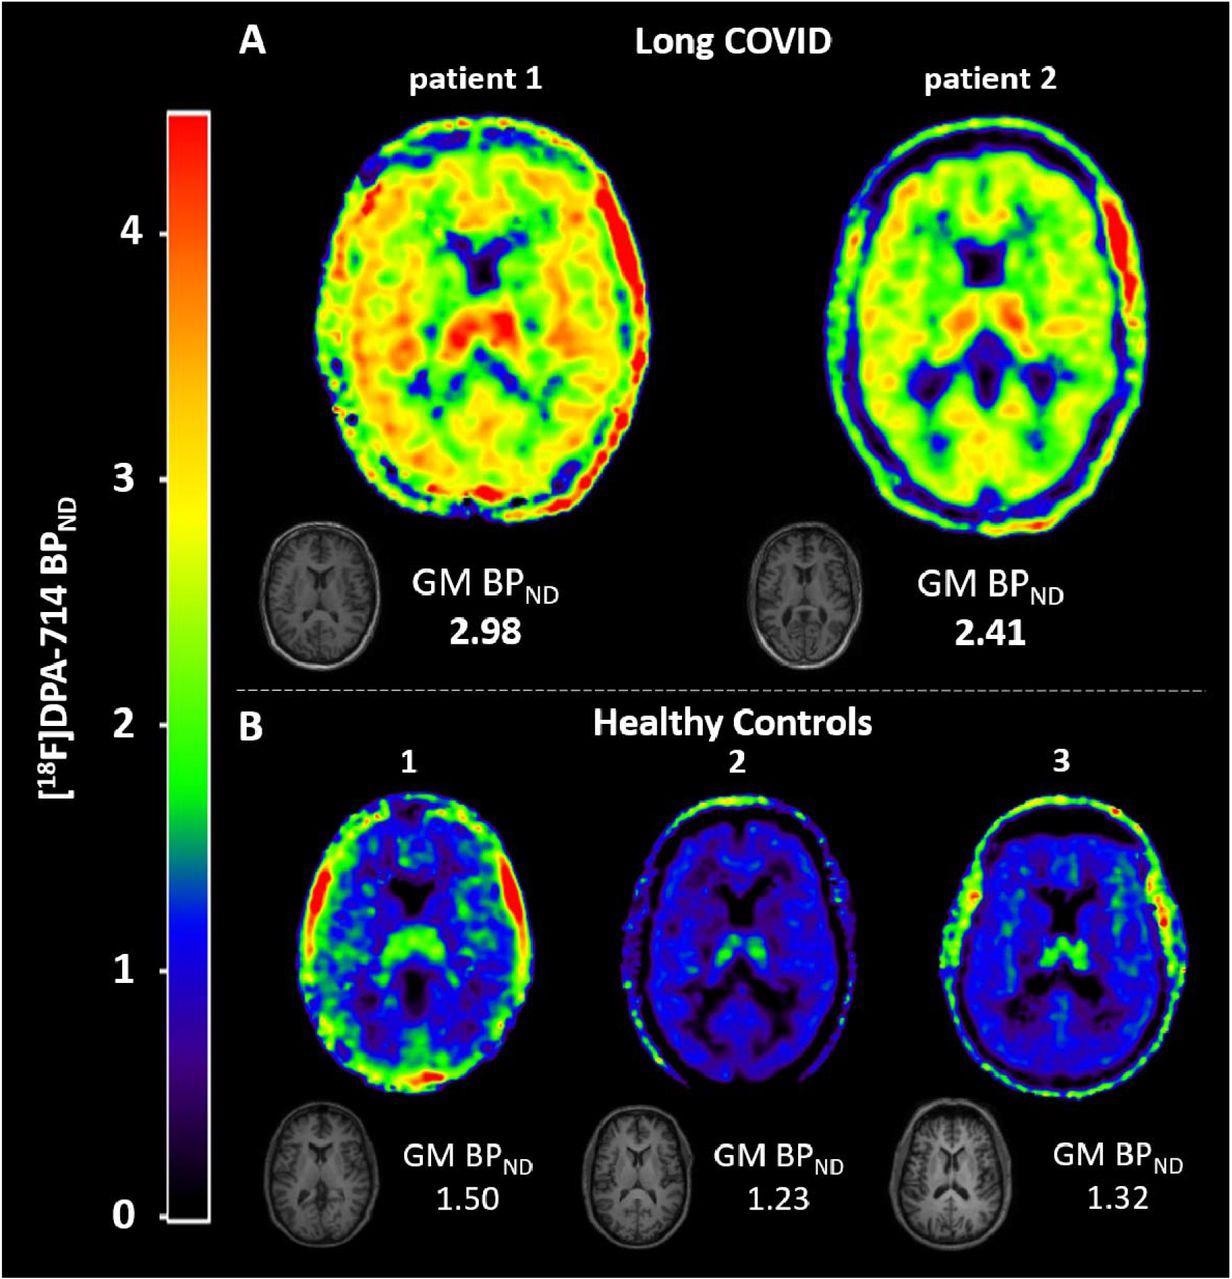

Neuroinflammation in two long COVID patients. To quantify [18F]DPA-714 binding in whole-brain gray matter (GM) we used a plasma input two tissue compartment model with blood volume parameter (2T4k_VB). All quantitative whole-brain grey matter binding potential (BPND (=k3/k4)) values reported are estimated using 2T4k_VB. For visualization purposes we generated volume-of-distribution (VT) images using Logan plot analysis (11), using t* = 10 min, and divided those images by the whole brain grey matter k1/k2 ratio obtained by the plasma input 2T4k_VB model, following subtraction of 1. By doing so, Logan VT images were corrected for the non-displaceable distribution volume resulting in BPND (=k3/k4) images for illustrative purposes. (A) T1-weighted MRI and parametric images of [18F]DPA-714 binding in the brain of two long COVID patients. Higher binding potential (BPND) values indicate more tracer binding and thus higher levels of neuroinflammation. Long COVID patient 1 showed severely elevated binding in all brain regions compared to the healthy control subjects. Long COVID patient 2 also showed elevated binding, with higher BPND values than the healthy control subjects. (B) T1-weighted MRI and parametric images of [18F]DPA-714 binding in the brain of three healthy control subjects.

The MRI of the healthy control subjects and the first long COVID patient was consistent with age; however, the MRI of the second patient had mild atrophy in the parietal region. Furthermore, the first patient showed severely elevated [18F]DPA-714 binding in all brain regions. Compared to healthy controls, BPND (=k3/k4) values obtained from the 2T4k_VB model in the first patient were increased by 121% on average, whereas the same values for the second patient increased on average by 79%.